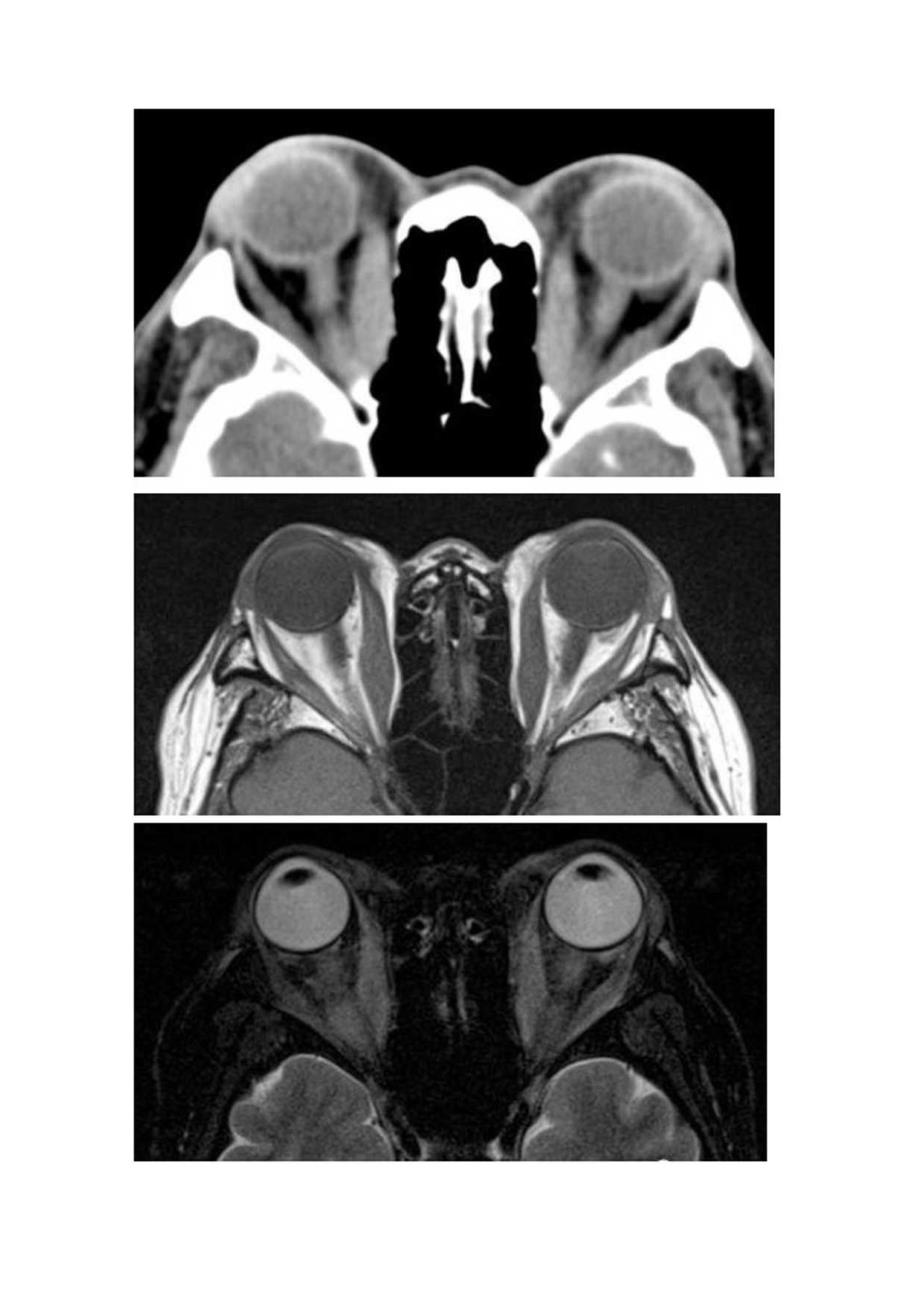

1、临床眼眶炎性假瘤病理、影像学表现及鉴别诊断可乐瓶征指轴位扫描时甲状腺眼病(thyroideyedisease)中眼眶肌肉的外观,肌腹随着肌腱插入的增加而扩大、增粗,肌腱附着处正常,表现为传统可口可乐瓶的样子。尤其是内直肌的增粗,且眶内侧壁骨质菲薄,长期眶压升高,致筛骨纸板向筛窦弧形凹陷,双侧对称。肌肉的增粗遵循缓慢模式IWS1.OW”。肌肉增粗的性质十分重要,是将其与眼眶炎性假痛区分开来的主要表现之一,与甲状腺眼病不同,炎性假痛的肌瞰也受累并增粗。甲亢突眼是成年人最常见的眼眶病之一,属于自身免疫性疾病。大多数患者可有甲状腺功能异常的临床或实验室检杳表现,但即使在甲状腺功能正常的情况下,也可能发

2、生眼眶疾病。甲状腺相关眼病是引起单眼或双眼突出的常见原因。在急性期,主要的原发改变是炎症,由于眼外肌肥大和眶脂肪容积增加而导致的体积效应,以及肌肉改变产生的运动受限。其次为眼应依从性的改变和由于眼眶缺乏淋巴回流而导致不同程度的瘀血。影像表现:1、冠状位可显示各条眼外肌增粗,甚至少数患者可累及上、下斜肌。2、轴位可较好的显示内、外直肌增粗,睚内侧壁骨质菲薄,长期眶压升高,致筛骨纸板向筛窦弧形凹陷,双侧对称,呈“可乐瓶”征。3、眼球突出严重者,视神经受到牵拉失去生理弯曲,呈直线状。re出力外t联线B为仃角黑到灰线的n即IIlII7夹电,EF为左窜”夹电中m人正常眼球突出度双限在I”ISl鉴别诊断:

3、肌炎型炎性假瘤疼痛无痛性突眼活动性疼痛病程发病缓慢多急性甲功异常正常激素治疗无效有效肌腹和肌腱同时增粗,且形态不规则眠后脂肪间隙受累,可伴视神经增粗、眼环增厚眼外肌改变肌腹增粗为主,肌腱附着处正常眶内结构受累多无随后脂肪间隙受累及视神经培粗眼眶炎性假痛(Orbitalpseudotumor)或称特发性眶部炎症,0前多数学者认为炎性假瘤是一种免疫反应性疾病。炎症表现为急性、亚急性或慢性,可单侧或双侧交替发生。病变部位可局部发生;但常多部位发生,包括肌炎、泪腺炎、巩膜周围炎、视神经鞘炎,多伴有脂肪炎性浸润。肌炎型表现为:一条或数条眼外肌增粗,以上直肌和内直肌多见,典型者为肌腱和肌腹同时增粗,边缘多模糊,不整齐。